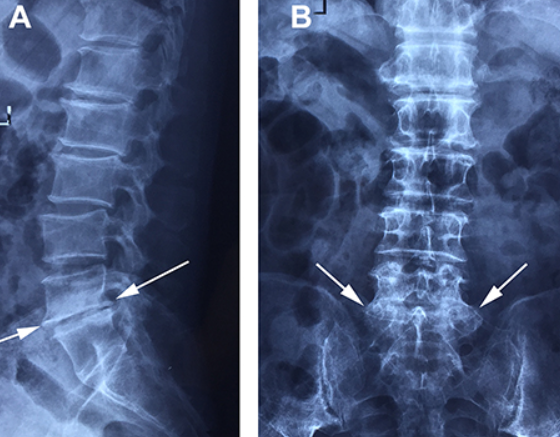

X-ray 검사를 통해 척추 간격 감소 여부를 확인합니다.

CT, MRI 등 영상검사를 통해 디스크 탈출의 위치와 정도를 정확히 평가합니다.